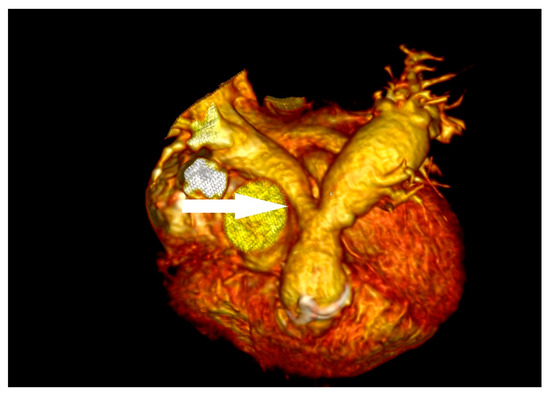

3.4. Case 4